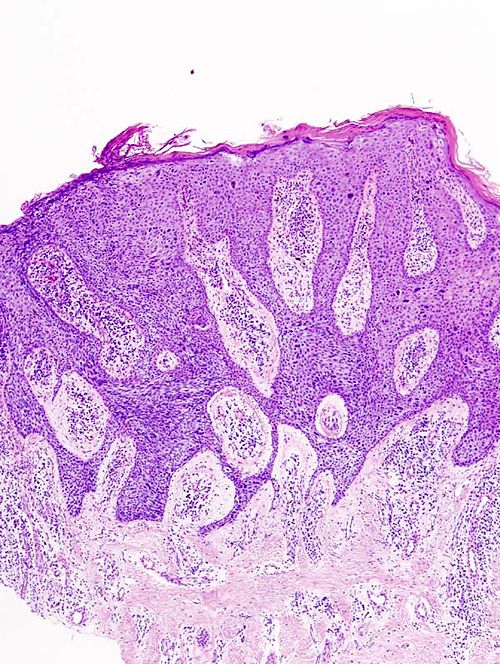

69 year old man, fisherman of 50 years, skin lesion

Back, 1 cm x 1 cm lesion

Low magnification. H&E stain.

This is the early stage of a malignant lesion